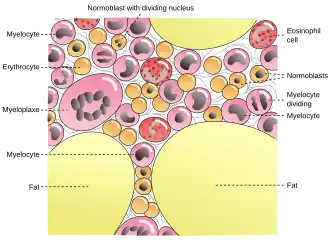

В живых организмах железо является важным микроэлементом, катализирующим процессы обмена кислородом (дыхания). Основным внутриклеточным депо железа является глобулярный белковый комплекс — ферритин. Недостаток железа проявляется как болезнь организма: хлороз у растений и анемия у животных.

Обычно железо входит в ферменты в виде комплекса, называемого гемом. В частности, этот комплекс присутствует в гемоглобине — важнейшем белке, обеспечивающем транспорт кислорода с кровью ко всем органам человека и животных. Именно он окрашивает кровь в красный цвет.

Железо в организме человека

В организме взрослого человека содержится около 3—4 граммов железа[51] (около 0,005 %), из которых только около 3,5 мг находится в плазме крови. Гемоглобин содержит примерно 68 % всего железа организма, ферритин — 27 %, миоглобин — 4 %, трансферрин — 0,1 %. Источниками железа при биосинтезе железосодержащих белков служат железо, поступающее из пищи, и железо, освобождающееся при постоянном распаде эритроцитов в гепатоцитах (клетках печени) и клетках селезёнки[52].